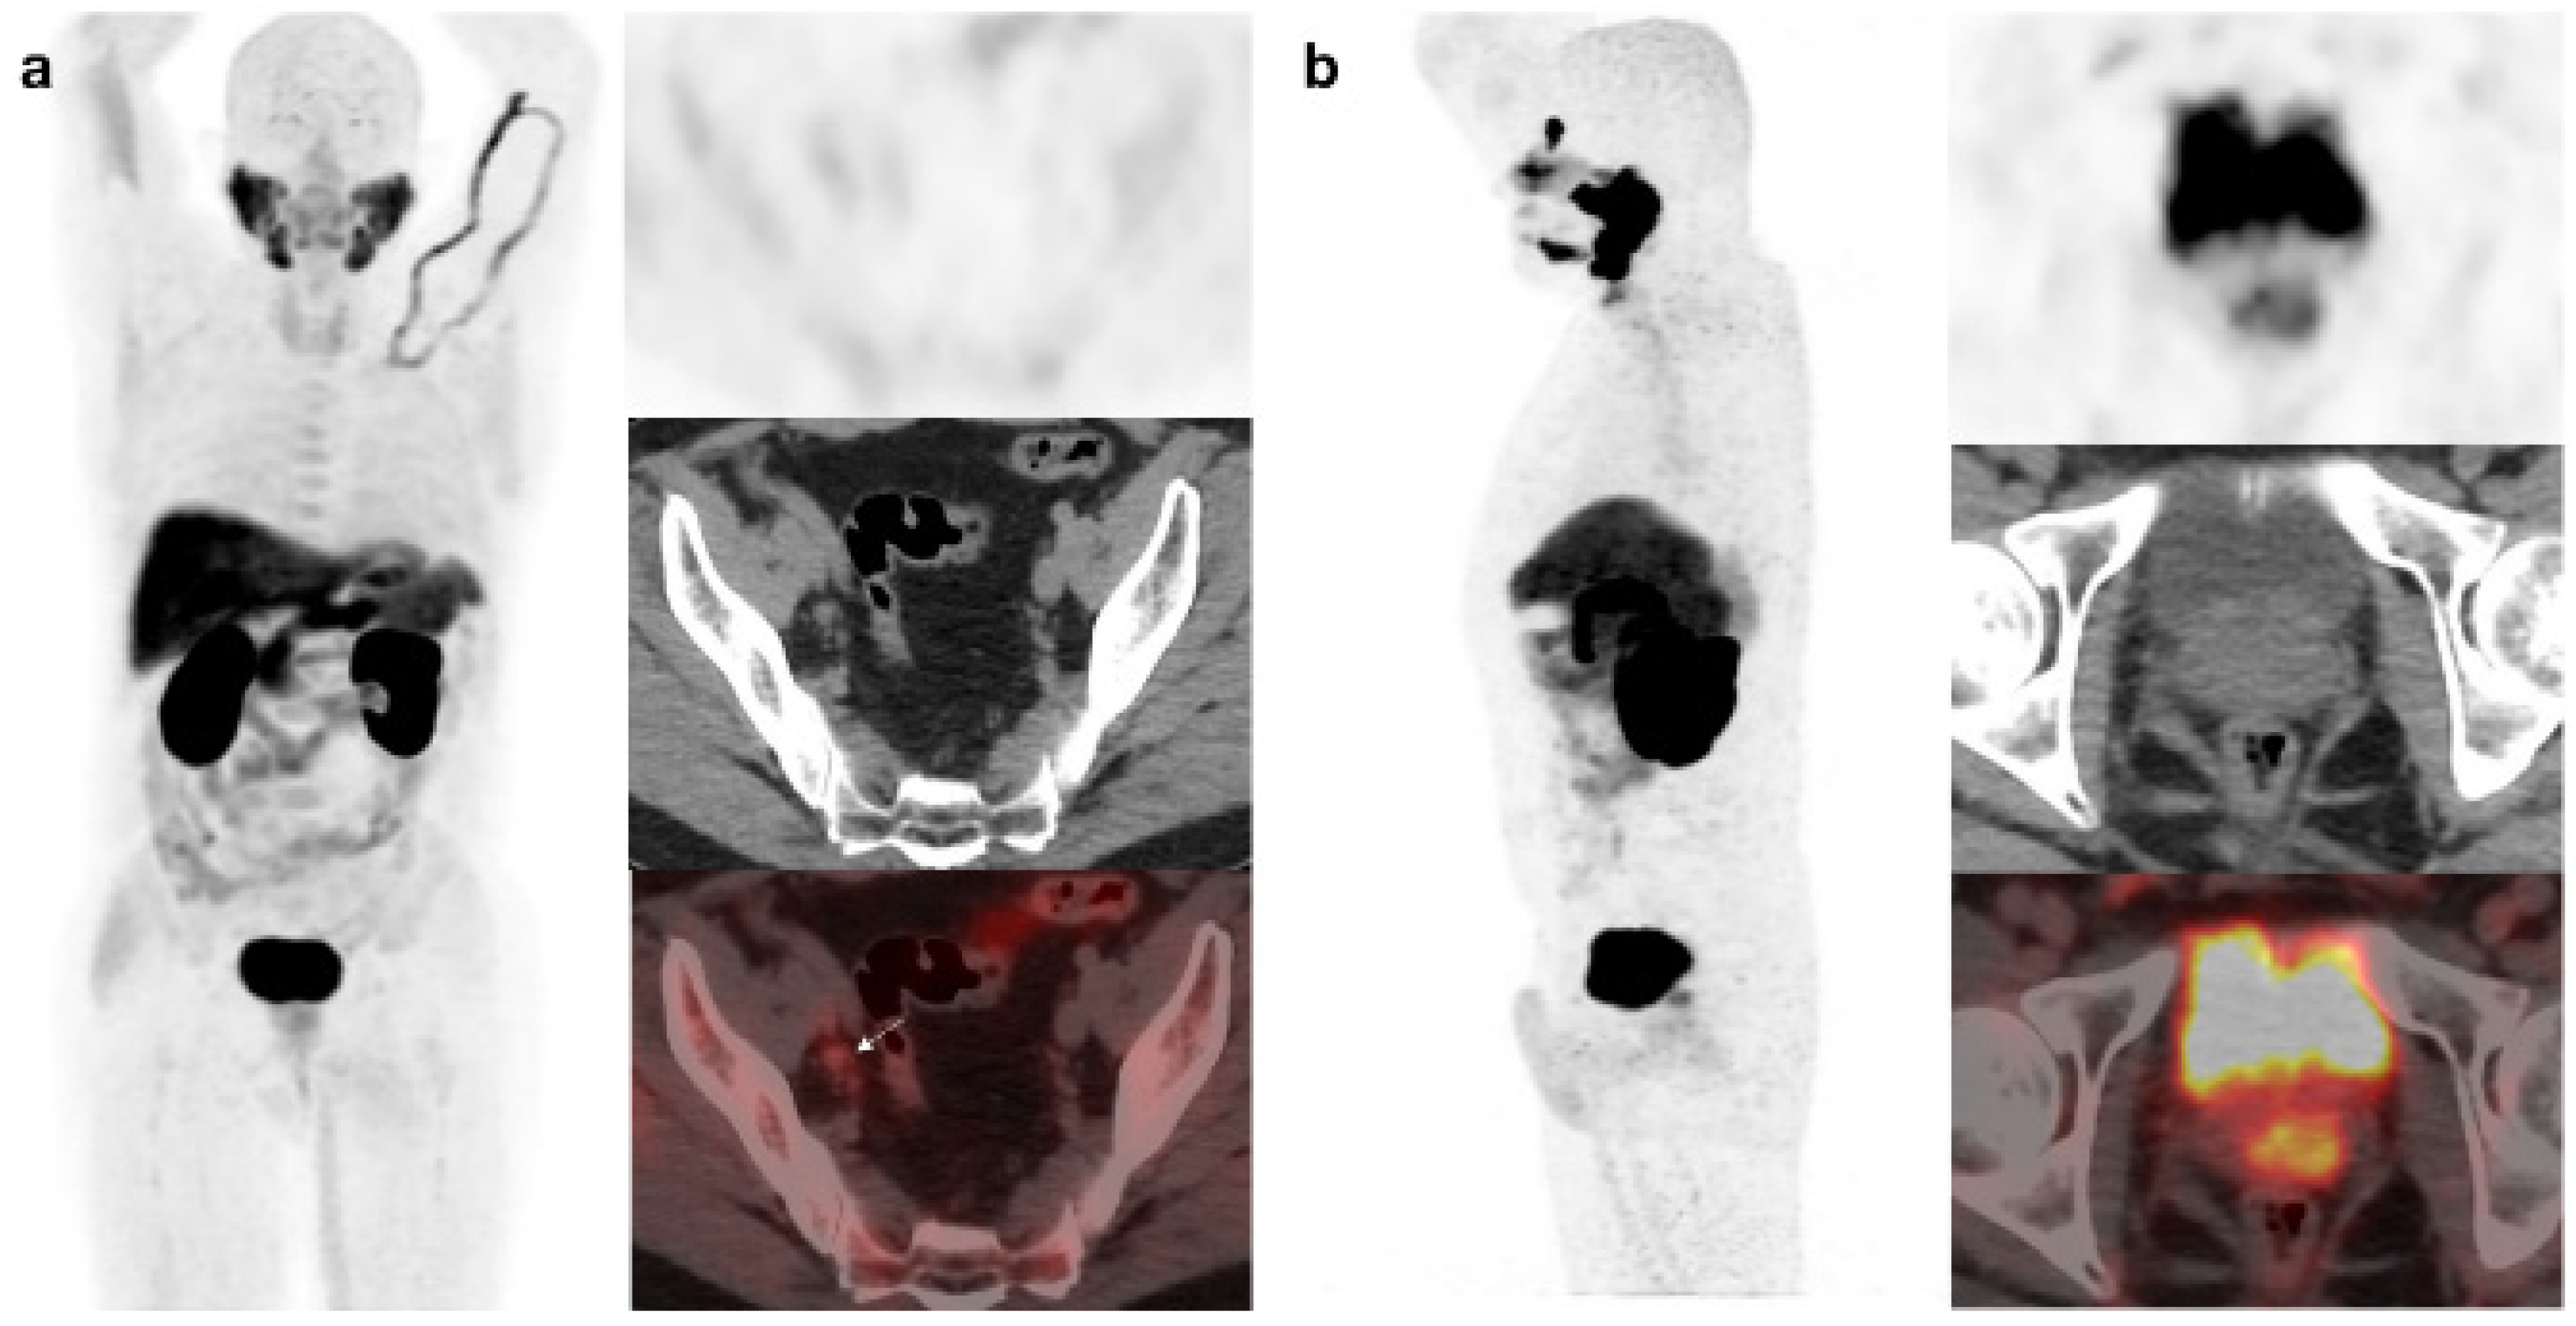

18F-DCFPyL-PET/CT was negative in 49/138 patients (7 low, 14 intermediate and 28 high risk). Follow-up was adopted in 29 patients (4 positive 18F-Fluorocholine-PET/CT) and 20 intermediate/high risk patients underwent treatment (12 prostatic fossa radiotherapy, 8 ADT, 1/8 choline-positive). Regarding the false positive, six patients with positive 18F-DCFPyL-PET/CT (2 prostate gland, 3 bone and 1 rectum) had a normal MRI (Figure 5) (Figure 6). Ten patients were choline-positive and considered false positive (2 prostate gland, 5 lymph nodes, 2 bone, 1 pelvic mass) due to 18F-DCFPyL PET/CT result, biopsy or clinical follow-up.

Figure 6. 56-year-old patient. PCa (Gleason 6) treated with braquitherapy. BCR (PSA: 5.4 ng/mL, PSAdt 6.17 mo, PSAvel 0.55 ng/mL/mo). 18F-Fluorocholine (a) showed prostate gland uptake and right external iliac lymph nodes metastasis (arrow). One month later the patient was also scanned with 18F-DCFPyL (b) revealing only prostate gland pathological tracer uptake. Prostate biopsy was negative (false PSMA positive). Follow-up was decided and PSA level keeps oscillating (4–5 ng/mL) with an additional negative 18F-DCFPyL PET/CT one year later.